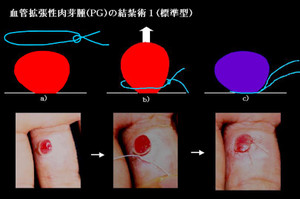

えぬくりブログ: 毛細血管拡張性肉芽腫 化膿性肉芽腫。

えぬくりブログ: 毛細血管拡張性肉芽腫 化膿性肉芽腫。

血管拡張性肉芽腫の治療芳仁皮膚科医院院長 張賢二のブログ。